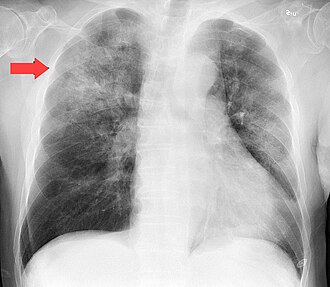

Cabe señalar que la neumonía es una enfermedad que provoca la inflamación de los pulmones por la presencia de una infección producida por virus o bacterias, misma que con los equipos adecuados, principalmente placas torácicas o radiografías se puede detectar a tiempo y detener por completo con el suministro de un antibiótico, por ello si la enfermedad se diagnostica a tiempo, reduce su mortalidad en un 42% en los niños de 2 años o menos.